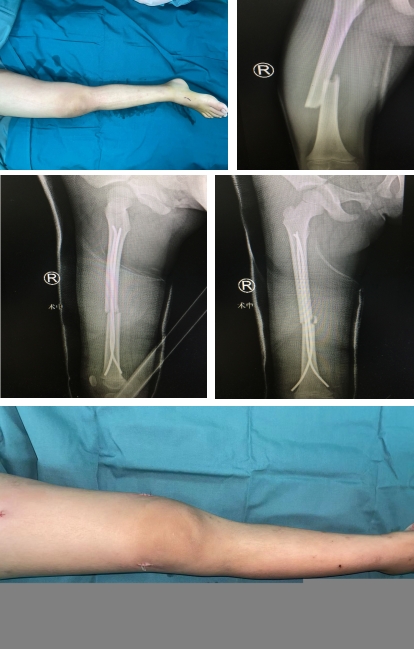

然而,手术并不一定是最佳选择。许多患者家属更愿意选择保守治疗或微创治疗。为了满足这一需求,我们采用了微创小切口治疗的方法。这种方法伤口小、恢复效果好,并且能极大地减少手术创伤。术后,我们会使用管型石膏进行外固定,有助于患者的快速恢复。

这种治疗方法有许多优点。首先,术后伤口小,患者疼痛轻,这大大减轻了孩子的痛苦。其次,恢复时间短,住院时间短,家长可以更快地让孩子回到正常的生活中。即使在严重的情况下,需要切开钢板进行固定治疗,我们也选择美容缝合的方法,以减少伤口愈合时的瘢痕增生,让孩子在恢复后能拥有更美观的皮肤。